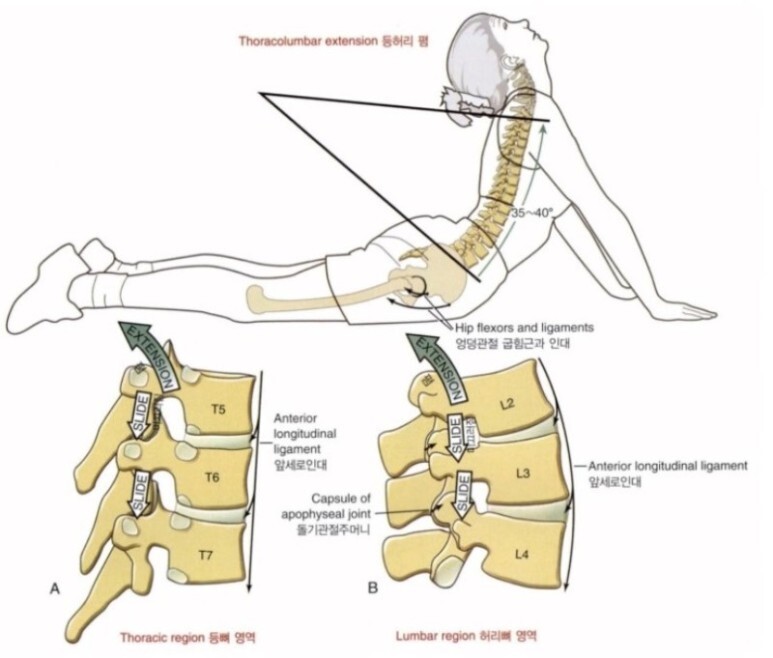

흉추의 스트레칭을 위해서 스핑크스 스트레칭을 무리하지 않게 꾸준히 해줄 수 있습니다.

폼롤러를 이용하여 흉추전만을 유도하고, 척추를 자극하여 혈류를 증가시키고, 척추 주변의 근육들을 마사지하는 효과가 있습니다.